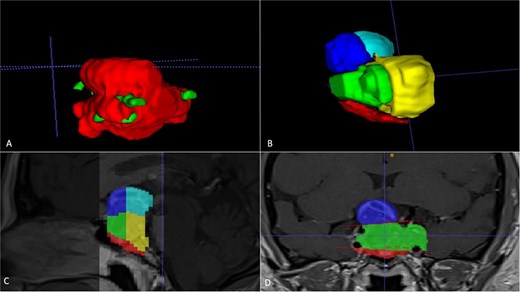

A 42-year-old patient who suddenly presented with headache and visual disturbances. The examination confirmed bitemporal hemianopsia, as well as bilateral papilledema. An MRI study obtained the following sequences: T1, T2, and T1 with contrast (Fig. 4). Manual 3D segmentation was performed to observe the intratumoral components and classify the different anatomical portions of the tumor, as well as its total estimated tumor volume and area (Fig. 5 and Table 2). The importance of reconstruction, in this case, lay in knowing the areas that were possibly not going to be so easily accessible through this endoscopic approach, as well as in calculating the volume of the tumor per segment and the possibility of having residual tumors in less accessible segments.

Manual planimetric volumetric segmentation. (A) Calculation of total tumor volume (red) and its relationship with the internal carotid artery (green). (B) Volumetry by zones. (C and D) Areas shown in sagittal and coronal planimetry.

| Geometric volumetry . | 3D volumetry . | Zone 1 Red (Intraspenoidal) . | Zone 2 Green (Intercarotid) . | Zone 3 Blue stronge (Supracarotid suprasellar) . | Zone 4 Yellow (Retrocarotid intraselar) . | Zone 5 Blue clear (Supraselar retrocarotid) . |

| 16 cubic centimeters | 21 cubic centimeters | 1.7 cubic centimeters | 3.7 cubic centimeters | 2.3 cubic centimeters | 9.7 cubic centimeters | 3.6 cubic centimeters |

The above is similar to our case number two, where the tumor is quite irregular in conventional ABC/2 volumetry; the real volumetric value of the tumor is underestimated; however, with our manual segmentation, the volumetry can even be measured by zones. In that case, it was important to measure the area where there was a greater possibility of residual tumor and thus be able to correlate it with the possibility of greater rates of total resection.